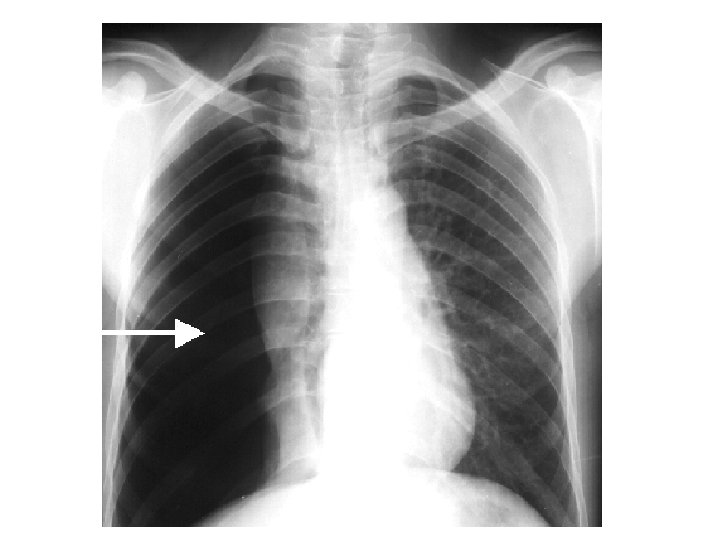

La plèvre • Séreuse entourant les poumons et se réfléchissant sur la paroi thoracique – Les deux feuillets de la plèvre (feuillet viscéral et feuillet pariétal) délimitent un espace normalement virtuel : l’espace pleural – Pneumothorax : présence d’air dans l’espace pleural – Hémothorax : sang dans la cavité pleurale – Pleurésie : épanchement inflammatoire (pus) dans la cavité pleurale